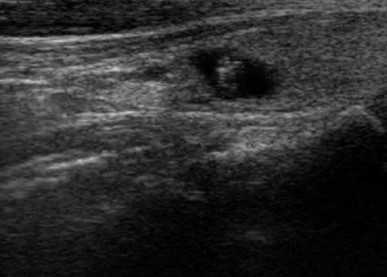

Образования, узлы. Во время сканирования доктор оценивает очаговую патологию и делает заключение в предположительном ключе. УЗИ щитовидной железы показывает:

Дифференциация опирается не только на серошкальные изображения, но и на данные ЦДК.

В пользу доброкачественности узлов свидетельствует совокупность признаков:

- изо-, гипоэхогенность;

- правильность формы;

- ровность, четкость контуров;

- превалирование длины над высотой;

- размеры менее 1 см;

- отсутствие кровотока.

Опухолевое поражение на сонограмме

По результатам УЗИ врач может предположить характер новообразования.

Рак щитовидной железы на сонограммах имеет:

- неоднородную преимущественно гипоэхогенную структуру,

- неправильную форму;

- размеры свыше 1 см - новообразования более 4 см всегда подозрительны на малигнизацию;

- множественные кисты/узлы, участки отложения кальция, фиброз;

- рваные, размытые контуры.

Явная асимметрия долей, лимфаденопатия, инвазия опухоли через собственную капсулу в соседние ткани свидетельствуют о продвинутых стадиях болезни.

В режиме ЦДК при злокачественном новообразовании видна нарушенная архитектоника сосудистой сети, избыточное количество артерий и вен, зоны некроза.

На УЗИ с эластографией опухоль имеет большую плотность по сравнению со здоровыми тканями.